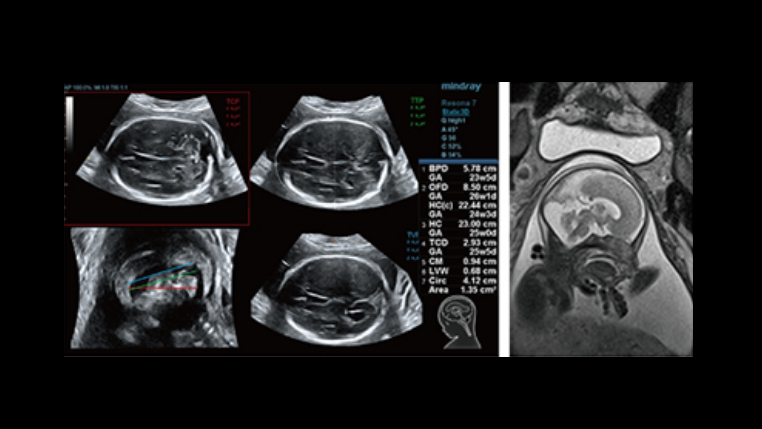

Automatic measurements of the most frequently examined parameters, including BPD, HC, FL, AC, OFD and even NT as early as 11 weeks, are available with a single click for higher productivity and reproducibility.